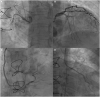

Case summary: We present the case of an 83-year-old woman with symptomatic severe AS, mildly decreased left ventricular ejection fraction and history of coronary artery bypass grafting with right internal mammary artery (RIMA) to the right coronary artery (RCA) and left internal mammary artery to the left anterior descending artery and further percutaneous coronary intervention (PCI) to the circumflex. First, we performed a transcatheter aortic valve implantation (TAVI) to treat the severe AS. Because of persistent symptoms despite good result, we then performed RA of the native RCA through the RIMA with a Guidezilla® guide extension catheter.

Discussion: A two-staged procedure of TAVI and PCI with RA of the RCA via RIMA was successfully performed. We decided to perform the PCI after the TAVI to allow a better haemodynamic tolerance of the complex coronary intervention. This procedure needs caution as the conduit is fragile and could be easily damaged during the RA. No data are available about feasibility and safety of RA through a native graft, but this could be a first step to consider it.